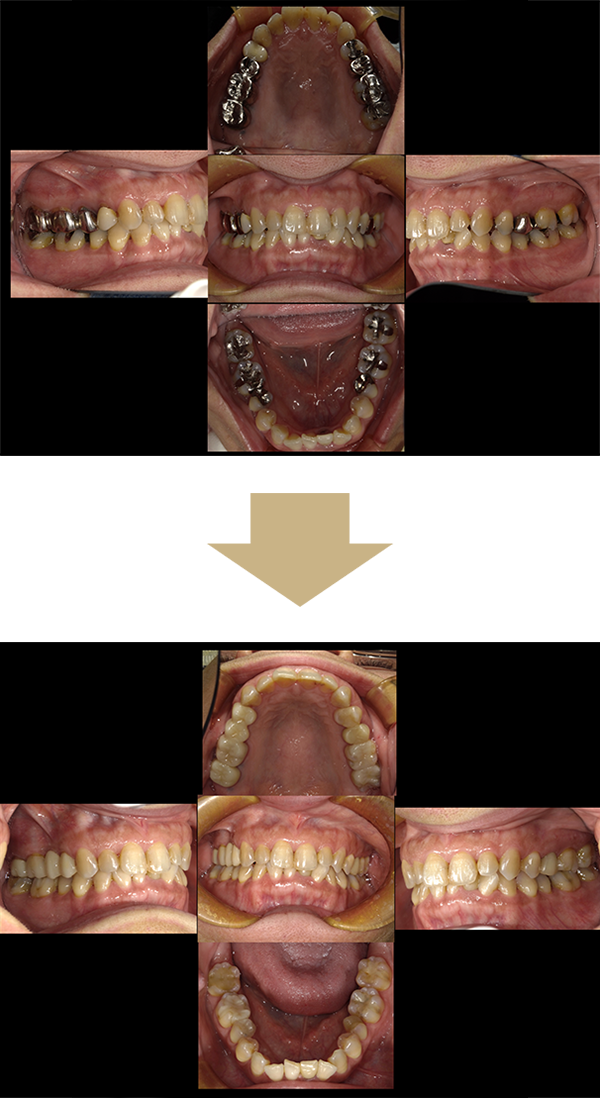

メタルフリー審美セラミック修復

施術の説明

昔むし治療をした際に歯に装着した金属修復物を、見た目が美しく金属アレルギーの心配がないセラミック修復物に変えることを希望して来院された患者さまの症例です。

歯を削るところ・型取りなど全ての処置でマイクロスコープを使用することで、より精密な治療が可能となります。

お口の中から金属が無くなり、笑顔に自信がもてるようになったと大変お喜びいただけました。

施術の副作用(リスク)

強い力がかかるとセラミックが割れることがある

施術の金額

1,100,000円(税込)